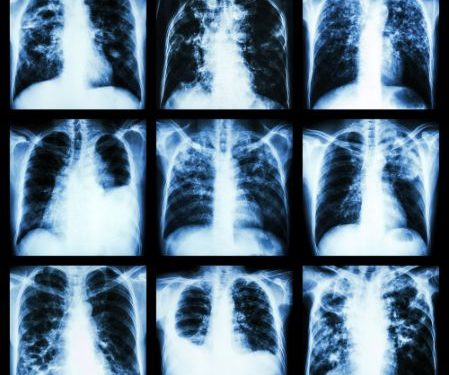

Your doctor can diagnose restrictive lung disease by reviewing your medical history and conducting a physical examination. You will also have a series of tests that can help them identify the cause of your breathing problems.

PFT: This is an imaging test that measures your lung capacity and diffusion capacity. It also checks for airway inflammation and changes in the strength of your respiratory muscles.